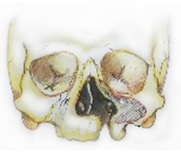

Szájpadhasadék és az ajak - veleszületett arc fejlődése

Ajak- - ajak-, hogy néz ki, mint egy keskeny nyílás vagy rés a bőr és a nyálkahártyák, a felső ajak. Cleft gyakran átterjed az orr, és megy a csont a felső állkapocsban.

Ez jelenti a szájpad vagy szájpadhasadék a lyukba. Farkastorok meghosszabbíthatja a szájpadlás szilárd (csont elülső része a szájpad) és / vagy a lágy íny (a lágy szájpadlás hátsó része).

Sok különböző formái szájpadhasadék és az ajkak, amelyek két csoportra oszthatók alapján etiológiája és morfológia. Ez ajak- és az alveoláris folyamatot, vagy anélkül szájpadhasadék, hasadék; izolált szájpadhasadék, melyek fordulnak elő egy későbbi szakaszban, miután a normális fejlődését a felső ajak és az állkapocs. Cleft lehet egy- vagy kétoldalas, valamint a teljes és nem teljes.